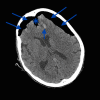

Tension pneumocephalus (TP) is the intracranial equivalent of tension pneumothorax. It is an unusual but life-threatening neurosurgical emergency, which has been described following head trauma, epidural injections or complicating neurological, spinal, craniofacial or sinus surgery. Unfortunately, the signs and symptoms of TP are non-specific and the diagnosis must be made by prompt recognition of the classic imaging signs of TP, allowing lifesaving emergency decompression. We present a trauma patient demonstrating the "Mount Fuji" sign on an unenhanced CT scan of the brain, which is reportedly specific for TP.